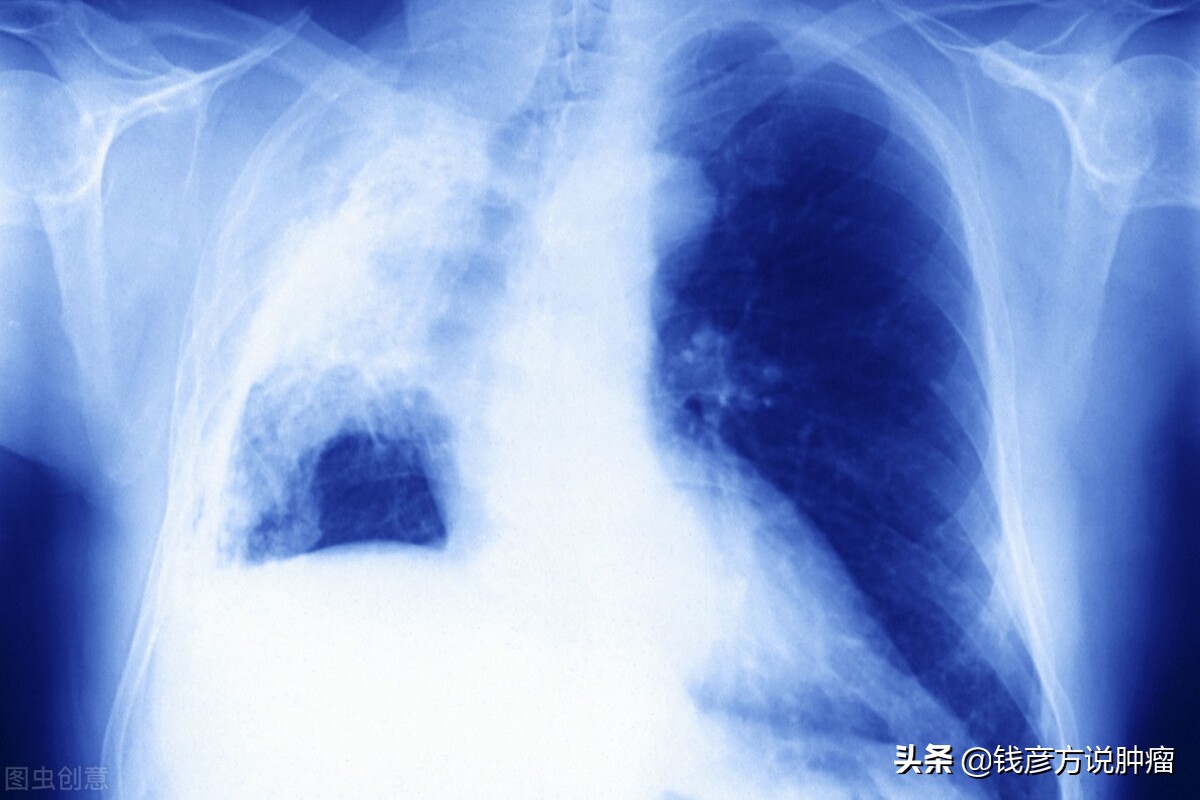

然后当年的10月8日例行检查,当时影像资料就觉得不太好,后来把加强CT的影像送到了北京,确定为肺癌了,一个月以后的病理确诊为肺大细胞神经内分泌癌,紧接着做了4次强化性的化疗,后来在2015年的3月份来到了这里寻求中医的帮助。

说到肺癌发病率是很高的,肺癌的类型也分为小细胞肺癌、非小细胞肺癌,包括鳞癌、腺癌,这名患者的肺癌类型是肺大细胞神经内分泌癌,还是比较少见的。